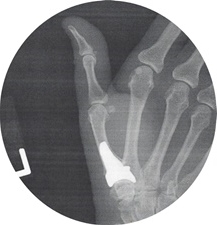

August of 2018

August of 2018:

As for the Levofloxacin damage

my wife had a Titanium Joint

implanted in her Left Hand.